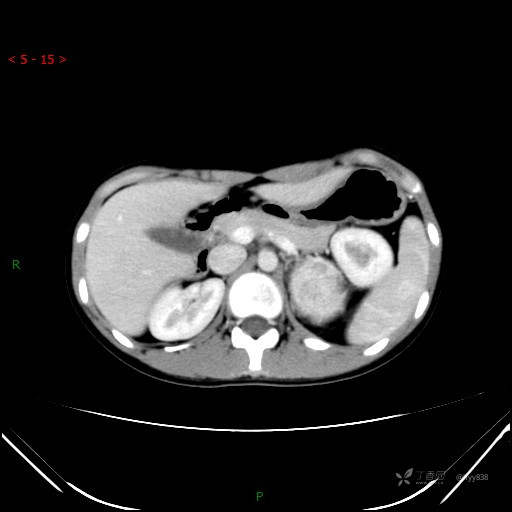

CT值